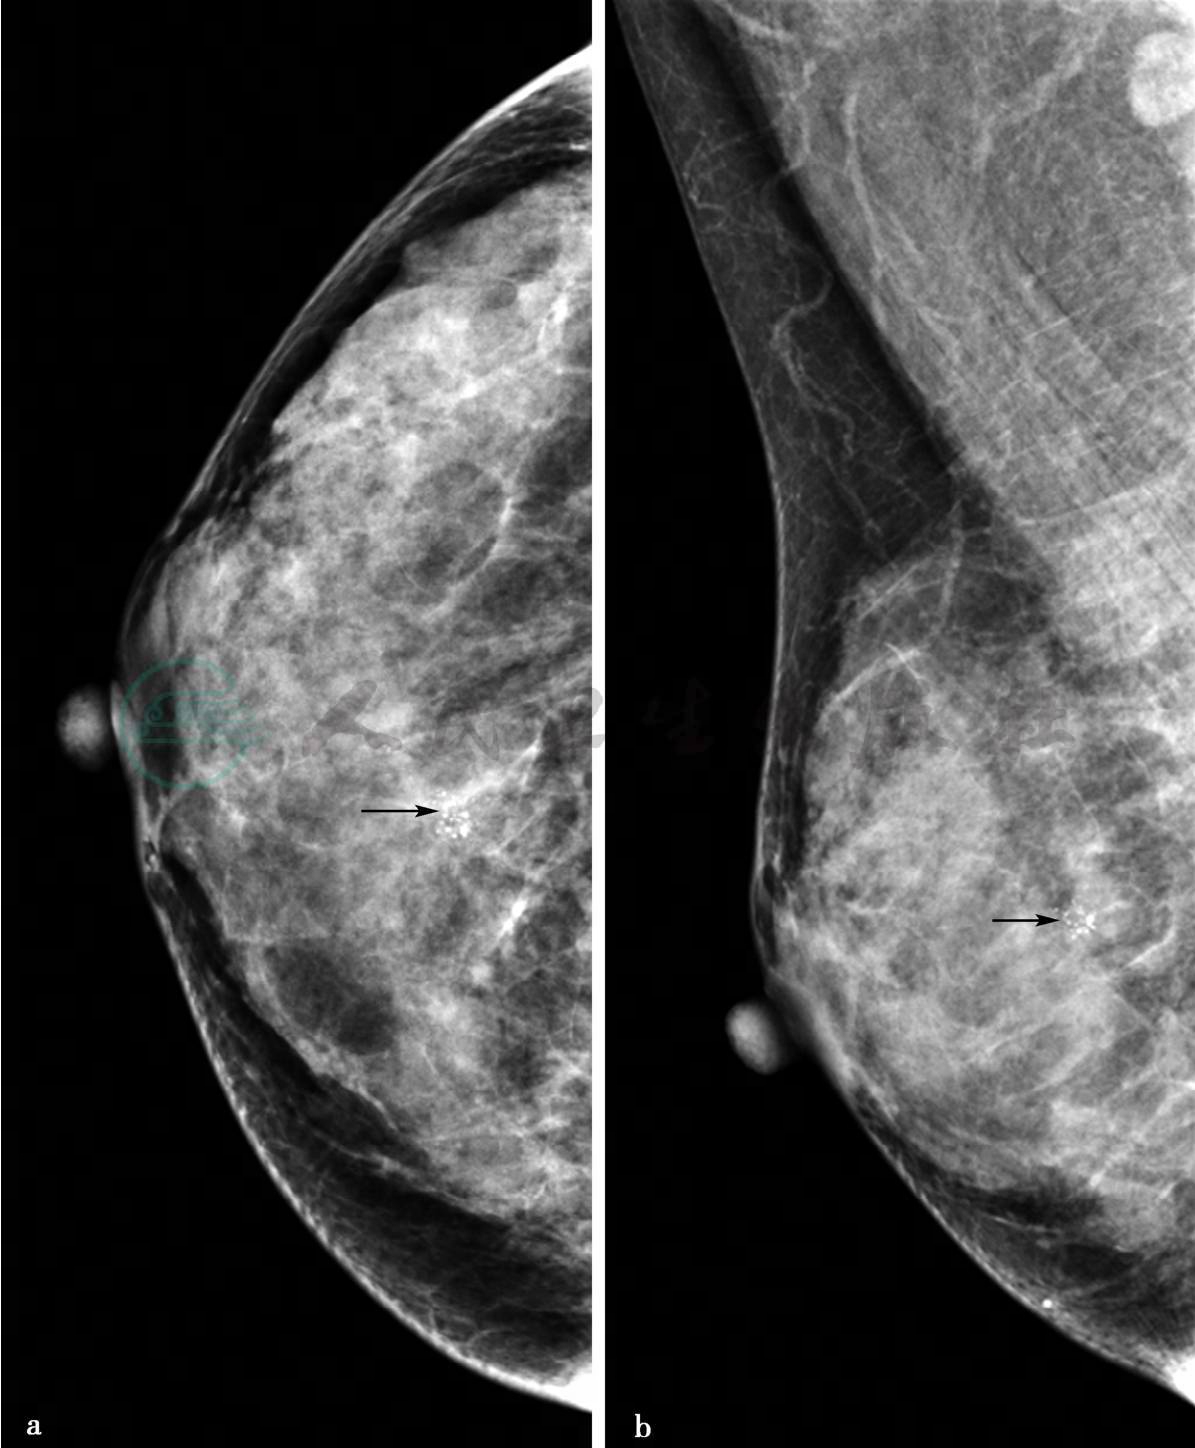

图1 图1a,右乳X线头尾位。图1b,右乳X线内外斜位。图1c,右乳X线头尾位钙化局部放大。图1d,X线导向下右乳钙化区域金属丝定位图像。图1e,右乳病变切除术后标本X线。X线显示双乳呈不均匀致密型乳腺,右乳内上方可见成簇不均质钙化,范围约0.8cm×0.7cm(图a、b、c箭头所示),其余未见明显异常